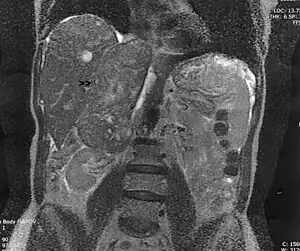

![]() | |

| Leiomyosarcoma of the adrenal vein. Coronal view of abdominal MRI. Tumor (arrow) extends from the superior pole of the right kidney to the right atrium. | |